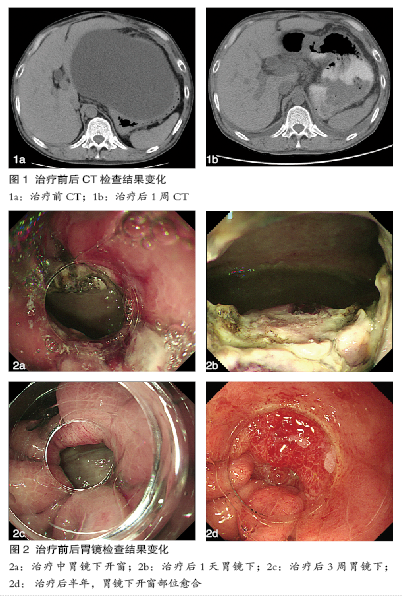

随着手术过程中大量脓液的释放,患者状态立即得到了改善,呼吸均匀了,脸色也很快变得红润,腹胀的症状明显减轻。术后第二日胃镜复查,见开窗处胃壁创无出血征象,开窗通畅,囊腔内已无脓性液体。术后患者病情平稳,无任何不适主诉,术后第十天患者出院。术后在半年里,患者一直在外地打工,无任何不适。期间进行了两次复查。半年后的复查证实囊肿已完全消失,胃黏膜已基本愈合(图1、2)。